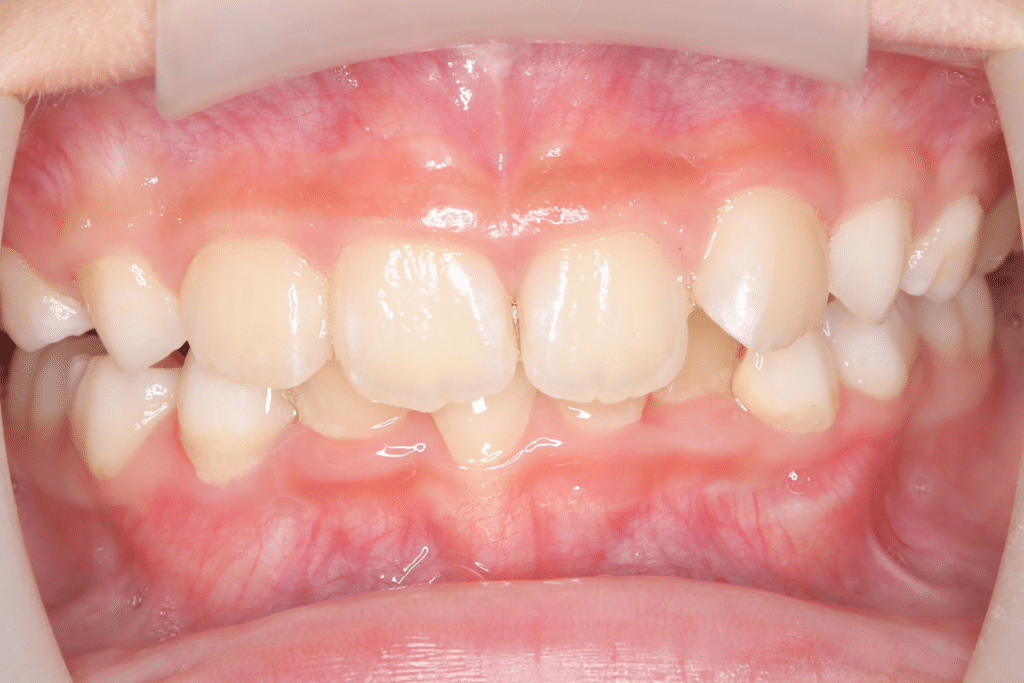

過蓋咬合

(9歳2ヶ月)

開始後0ヶ月

(開始後0ヶ月)噛み合わせの深さからくる咬合圧の強さと歯ぎしりを心配されていたため、歯ぎしりから歯を守りつつ、噛み合わせの深さを改善するためのマウスピースを使用開始。

いくつか方法がある中で、今回は保護者と患児の希望も含めて、過蓋咬合専用のマウスピースと、筋機能療法を併用し、顎の噛み合わせの深さを改善する方向で進めるプランで合意した。